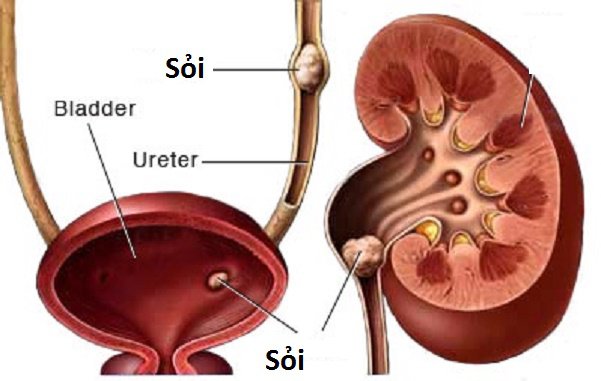

2. Sỏi thận

Bệnh sỏi thận là gì?

Sỏi thận gây ra nhiều khó khăn trong sinh hoạt hằng ngày

Sỏi thận hình thành khi các chất khoáng trong nước tiểu đọng lại ở thận, niệu quản, bàng quang,… các chất khoáng này lâu ngày hình thành những tinh thể rắng, kích thước có thể lên đến vài cm. Đối với những viên sạn, sỏi nhỏ thì có thể tống ra ngoài khi tiểu. Tuy nhiên, với những viên sỏi lớn thì có thể làm chèn, tắt đường dẫn nước tiểu và gây ra hậu quả khôn lường. Thêm vào đó những viên sỏi to khi di chuyển trong thận, bàng quang, nệu quản,.. suất hiện cọ sát, dẫn tới tổn thương.